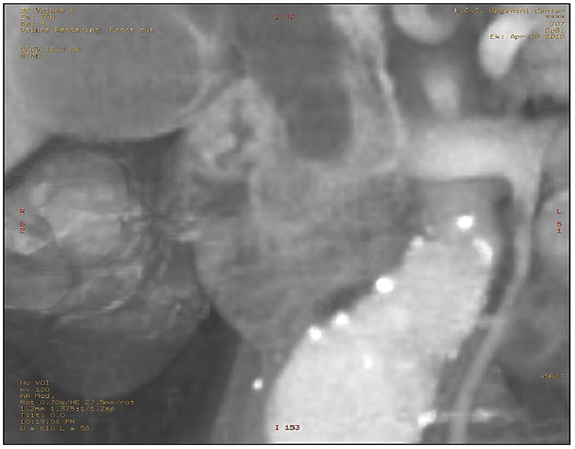

MSCT scan was performed unenhanced and on a on dynamic contrast-enhanced MDCT study with a volume of contrast medium (2mL/kg b.w) is given by rapid infusion (flow rate 4 mL/s) and MDCT is used in the parenchymal phase, with an imaging delay of aortic transit time plus 25 s, and in the venous phase (Figures 1-5). The cutoff of a distal segment of CBD and a dilatation of a CPD due to lateral compression from the pancreatic mass. The mass measured 16x10x17mm, without the infiltration of peripancreatic space. No distant metastases in the abdomen were seen, and no enlarged lymph nodes were noted.

Figure 1 Axial MDCT shows a double duct sign in pancreatic cancer.

Figure 3 Curved planar reformation shows the mass in the head of the pancreas with pancreatic duct obstruction due to the compression of its lateral wall, CBD dilatation with a curvilinear cut off sign. Fusiform aneurism of the suprabifurcational segment of the abdominal aorta with linear calcifications of the aortic wall.

Figure 5Curved planar reformation inverse gray shows more clearly the mass in the head of the pancreas.